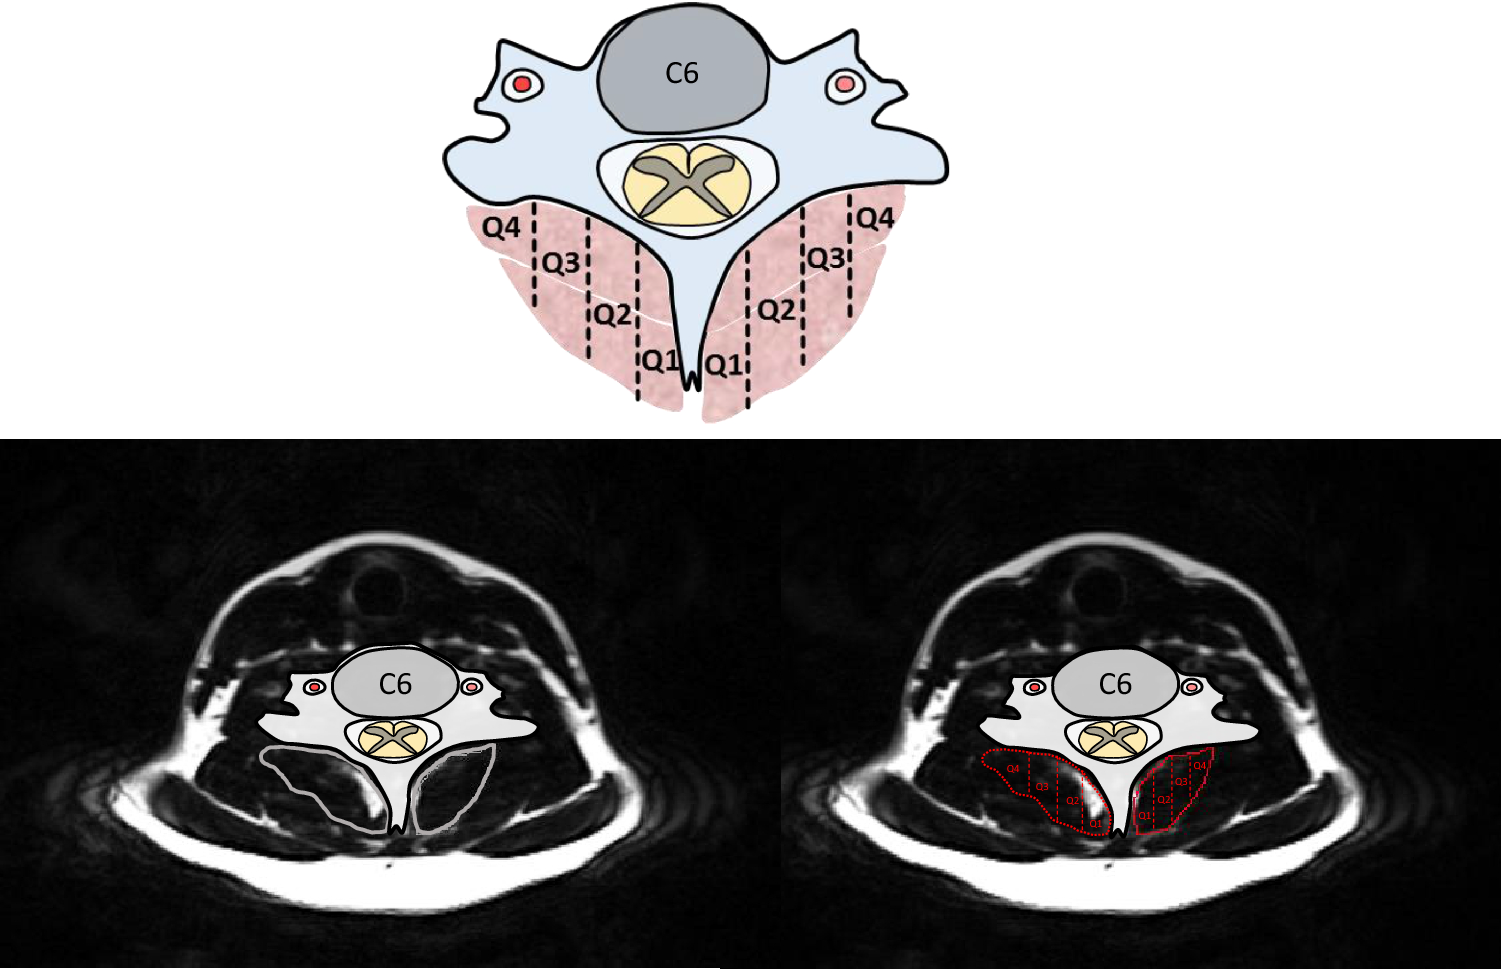

Figure 1

Deep cervical extensor muscle segmentation was delineated into the four quartiles, with Q1 being most medial (near the spinous process) and Q4 most lateral.